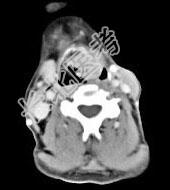

- 单项选择题男,53岁, 咽部不适半年余,近两个月感咽部疼痛, 声嘶,CT如图所示, 应诊断是 ( )

D、喉癌

E、梨状窝癌